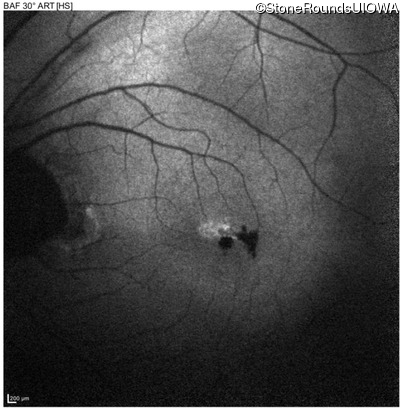

Blue Autofluorescence - Right - 20/32 -1 sc

Exemplar